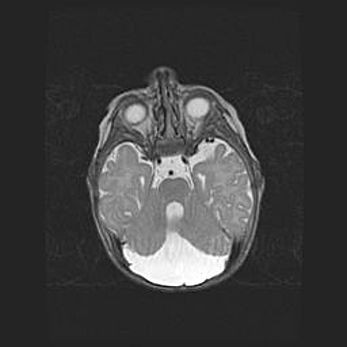

Подострая гематома правой гемисферы мозжечка.

Наружная гидроцефалия.

Возраст: 15 дней

Вес: 3100 г

Пол: женский

Окружность головы: 37 см

Срок гестации: 35-36 недель

При открытой наружной форме гидроцефалии у новорожденных расширяются и переполняются субарахноидные пространства.

Кровоизлияния в мозжечок имеют две клинико-анатомические формы: полушарные гематомы и кровоизлияния в червь.

К появлению этой патологии может привести: повреждения головного мозга, возникающие в результате асфиксии и гипоксии плода при беременности, или травмы во время родов. Редко гематома мозжечка может быть результатом первичной коагулопатии и сосудистой мальформации, диссеминированном внутрисосудистом свертывании, изоиммунной тромбоцитопении.